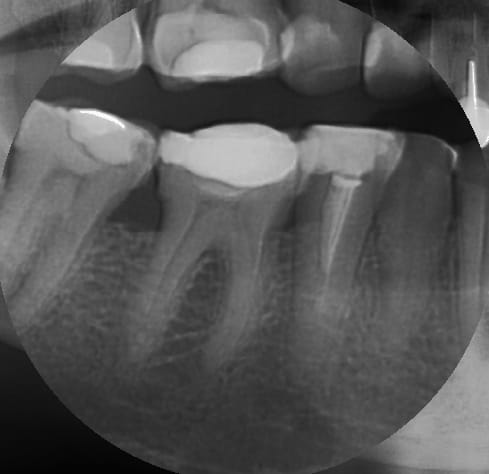

je fait extrêmement peu de tenon, mais tu nous présentes un travail soigné au moins d'un point de vue radiologique, sur la technique endo intrinsèque je laisse le soin a chacun de se faire une opinion